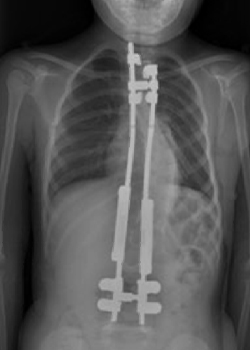

Growing rods are metal rods attached to the spine in an operation, that allow for continued growth of the spine. They are effectively an internal brace system to stabilise the spine, providing partial correction and stopping the curve from progressing. The rods are put in from the back of the spine and attached to the spine above and below the curve. The curve is partially corrected during the first operation.

The child returns every six months to a year to have the rods lengthened to keep up with the natural growth of the spine, whilst directing the growth into a more ‘normal’ line. This is a smaller operation, under general anaesthetic, and the child is usually in hospital just one or two nights.

Having growing rods does mean repeated surgical procedures and hospital admissions. There is also the risk that rods can break, although with development of instrumentation this is becoming less common. Most children will have to wear a brace to protect the instrumentation.